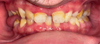

These anomalies caused right lingual interposition with marked anterior overbite, impairing phonation, mastication, and smile aesthetics. Posterior occlusal insufficiency alters balance and may predispose to temporomandibular disorders. The psychosocial impact of visible sequelae was also significant (Fig. 4).

Fig. 4 Intraoral frontal view in occlusion, highlighting anterior deep bite and right posterior open bite. |